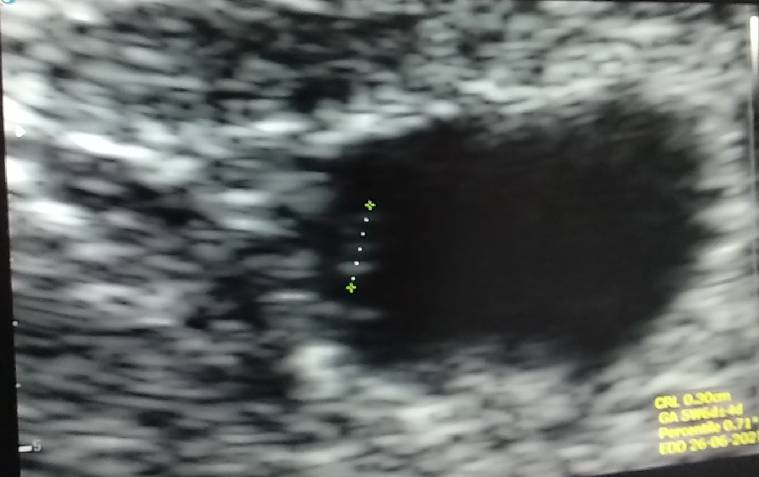

Jest kropek!! Do tego z bijącym serduszkiem [emoji3590] ciąża kilka dni młodsza według USG 6+1, termin na 24.06. Odetchnęłam, chwilowo jestem spokojna [emoji846] kolejna wizyta 20.11 o 15.30 [emoji846]Zobacz załącznik 1194573